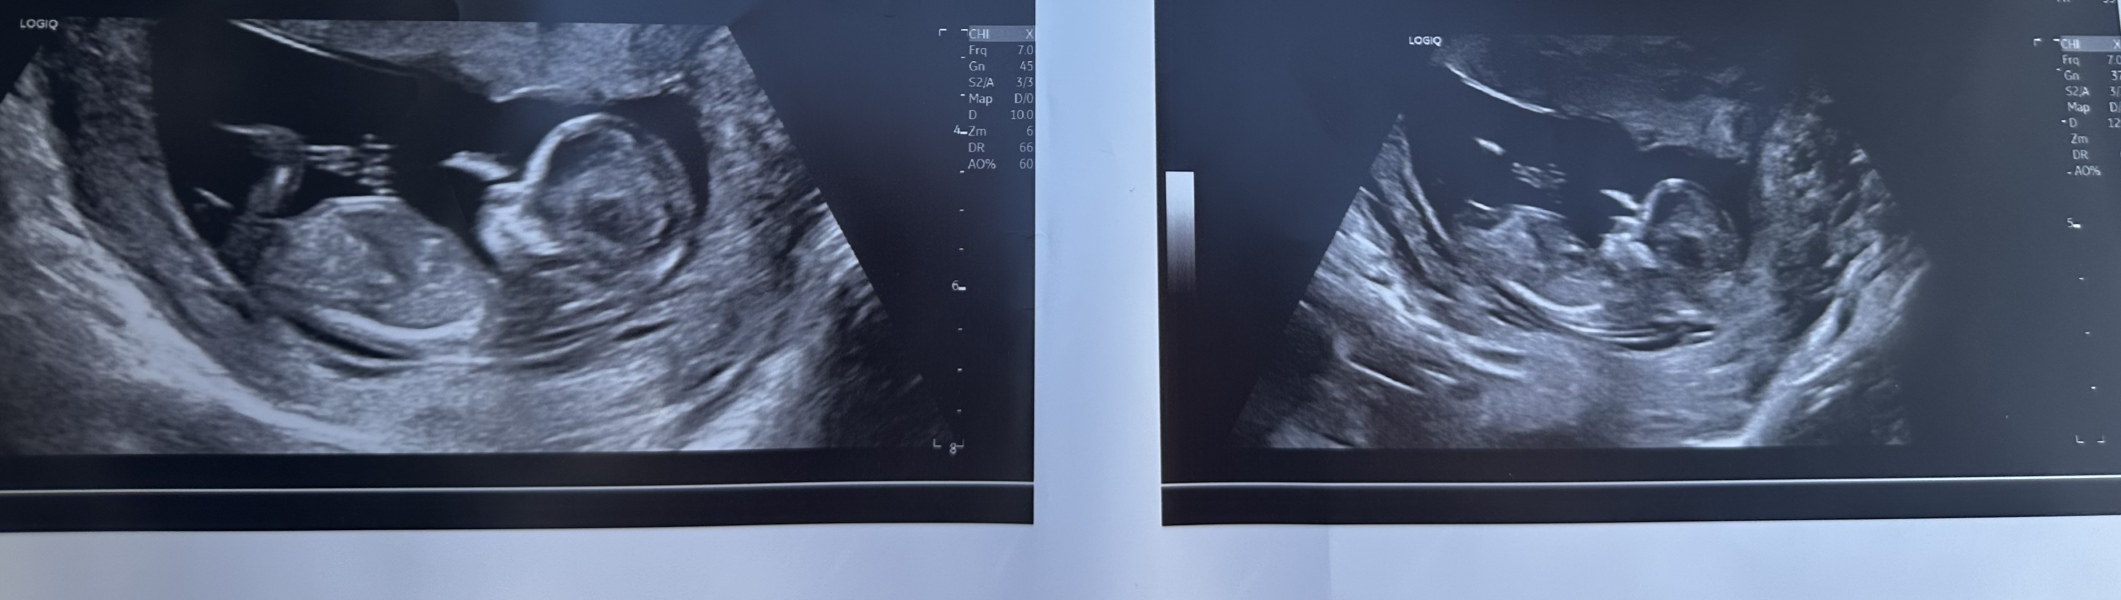

does anyone have any guesses of the sex? I am 12+2 xx